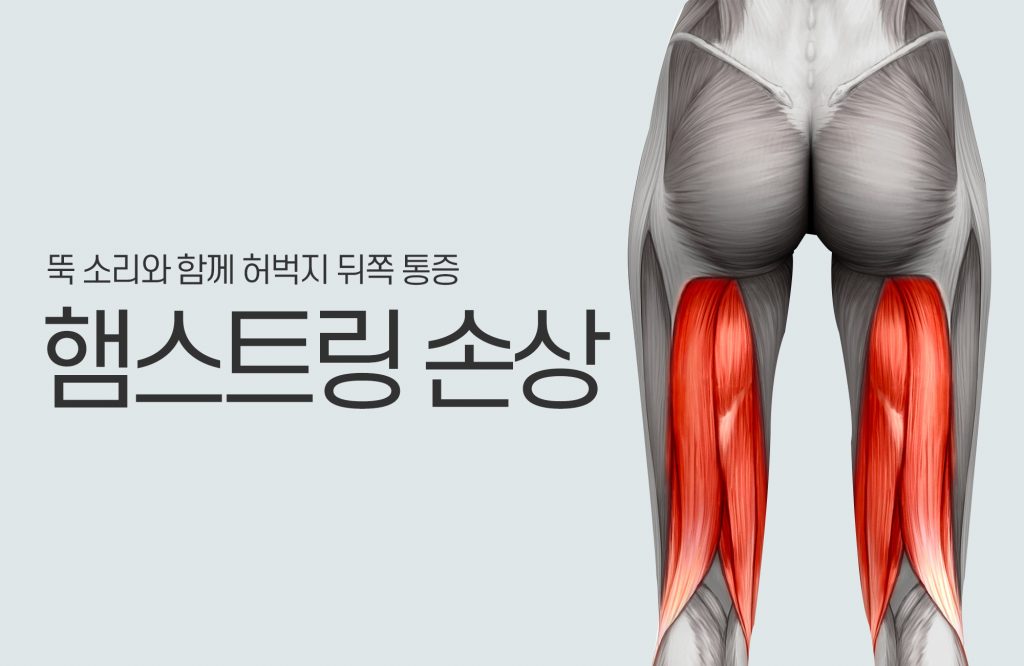

The feedback after the comeback seems to be good:) If you ride the link above, you will see a video of angle training at first, especially resistance in the tip range is inconvenient for tendons and ligaments, so recovery in the last range is absolutely necessaryWhile resisting an injured (right) elbow by a power band, especially when the elbow is pulled, instability increases and feels bad. Training such as fast pulling is essential because you have to build an elbow that can withstand such external resistanceLike one-handed training with aqua bags, it causes traction stress on the armsLike one-handed training with aqua bags, it causes traction stress on the armsIt doesn’t seem difficult to load your elbows with a different kind of aqua bag, but you won’t know until you hear the fact that water is hard to control where it jumps!one-handed kettlebell swingAquabag Training The work of creating a good transfer of force from the foot to the arm through the torso during rotationAquabag Training The work of creating a good transfer of force from the foot to the arm through the torso during rotationa task that bears no resemblance to the back throwing technique but is anatomically somewhat similar to the back throwing techniquea task that bears no resemblance to the back throwing technique but is anatomically somewhat similar to the back throwing techniquea task that bears no resemblance to the back throwing technique but is anatomically somewhat similar to the back throwing techniquePush and pull the training you do with the power band!Nordic hamstring training has a big impact on the elbow in the process of falling off.You may be traumatized because you injured your elbow while supporting your arm on the ground, but you can take your body back without any problems because you have eliminated the trauma through gradual training!A one-handed overhead presser needs some relative stretching for his or her class, but he or she never exerts 100 percent of his or her strength in sports. Still, for a firm elbow, you have to do stretching training. The main purpose is to prevent injury.”A one-handed overhead presser needs some relative stretching for his or her class, but he or she never exerts 100 percent of his or her strength in sports. Still, for a firm elbow, you have to do stretching training. The main purpose is to prevent injury.”A one-handed overhead presser needs some relative stretching for his or her class, but he or she never exerts 100 percent of his or her strength in sports. Still, for a firm elbow, you have to do stretching training. The main purpose is to prevent injury.”In judo, where landmine training rotation is very important, the rotation of the supporting legs and torso is very important. This coordination can lose a lot of energy without good mechanisms, so it doesn’t have to be a landmine. Think about how to improve this athlete’s specific strength.”It wasn’t a lot of time, but I feel good that you seem to be adjusting well after your comeback.”:) We will continue to communicate and manage for a successful comeback!Management is essential, even if you’re not necessarily a player. You have to understand the purpose of your training, whether it’s your elbow or shoulder, and you have to keep managing it so that it doesn’t cause problems again, especially as a degenerative problem :)트위의의 https://www.youtube.com/channel/UCiLHiCSnwY27HmJMN4GLcCQ?view_as=subscriber튜의 https://www.instagram.com/goodboy_workout/브로필 사진 https://blog.naver.com/bibazx123/221571488802타로필 사진 https://goodboyworkout.tistory.com스이지 않습니다. http://pf.kakao.com/_lexcgs카이지 않아요.open.kakao.com/o/sQHMkf8bSNS